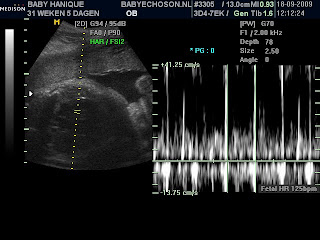

Ultrasound

Here's the pictures of the ultrasound. The first one is her face, she's looking right at the camera! The second picture is also her face but from the side.

Last Friday I had another check up and an ultrasound (I'll post some pictures later).

Everything is fine. I got the shot for rhesus. The baby is growing really well. She's about 1500 grams now. She's a busy little thing, moving and kicking all day long.